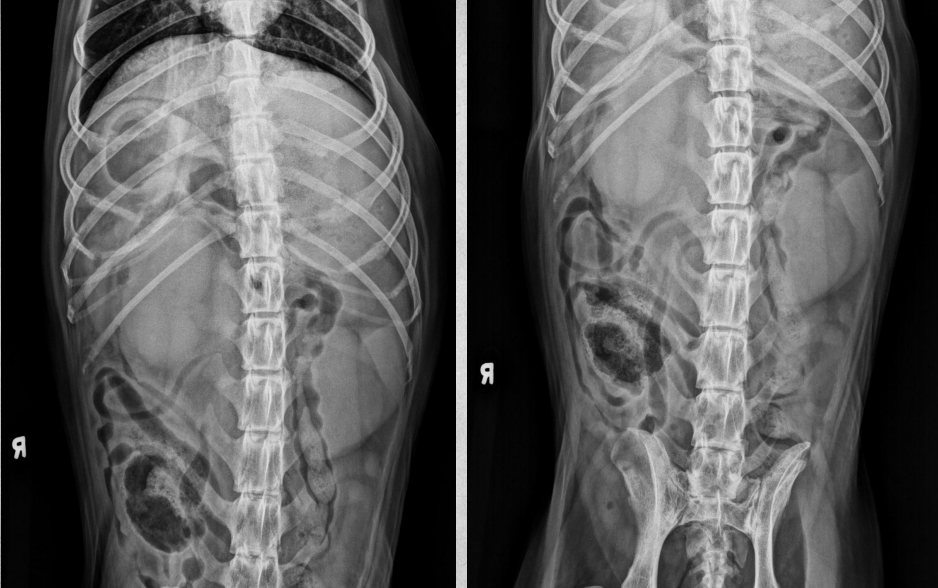

●9 yo mixed breed female dog

(sterilized)

●Increased ALP

● Impressive amount of subcutaneous and intra-abdominal fat.

● Enlarged liver – changed gastric axis pushed caudally, rounded edges, extending past the costal arch.

● At least two round soft tissue opacity structures superimposed on ventral liver (lateral view).

● Round soft tissue structure cranial to right kidney.

● Mass in adrenal gland or pancreas

● Hepatic nodules (benign vs metastatic disease)

SI gas is normal because bowels empty.